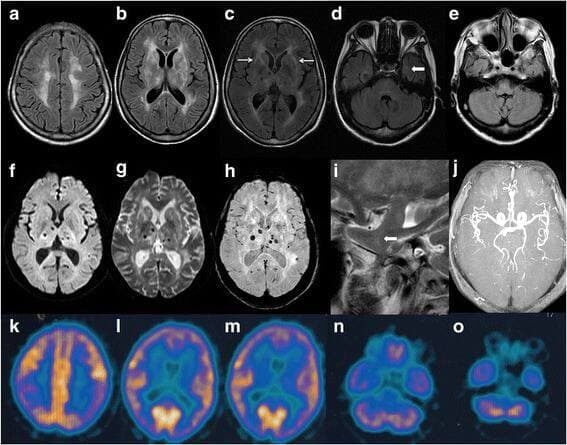

Фатальная инсомния представляет собой разновидность энцефалопатии, при которой происходит разрушение структур зрительного бугра-таламуса. Выделяют две формы данного заболевания: наследственную, которую и называют фатальной семейной бессонницей (FFI), и форму спонтанной ненаследуемой мутации-спорадическую фатальную бессонницу (sFI).

Основными методами диагностики FFI являются генетический анализ и МРТ, однако фатальная семейная бессонница сейчас считается неизлечимой. Лечение по большей части сосредоточено на облегчении симптомов и паллиативной помощи. В настоящее время основным направлением, предполагающим лечить заболевание, является генная терапия.